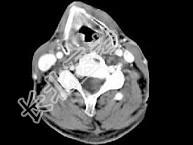

- 单项选择题男,63岁, 咽喉部不适约1年,近两个月经常咳嗽, 痰中带有血丝,CT如图所示, 最可能的诊断是 ( )

A、梨状窝癌

B、声门型喉癌

C、声门下型喉癌

D、声门上型喉癌

E、混合型喉癌